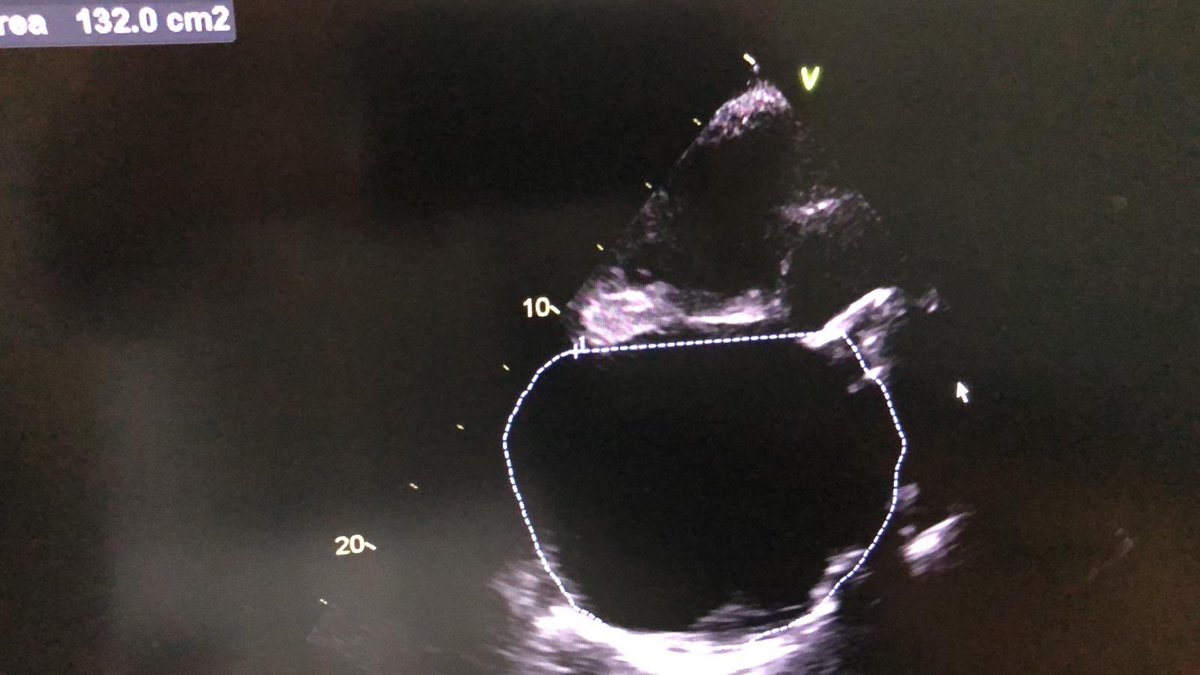

Biggest atrium ever seen 900ml. You think Feasible triclip?